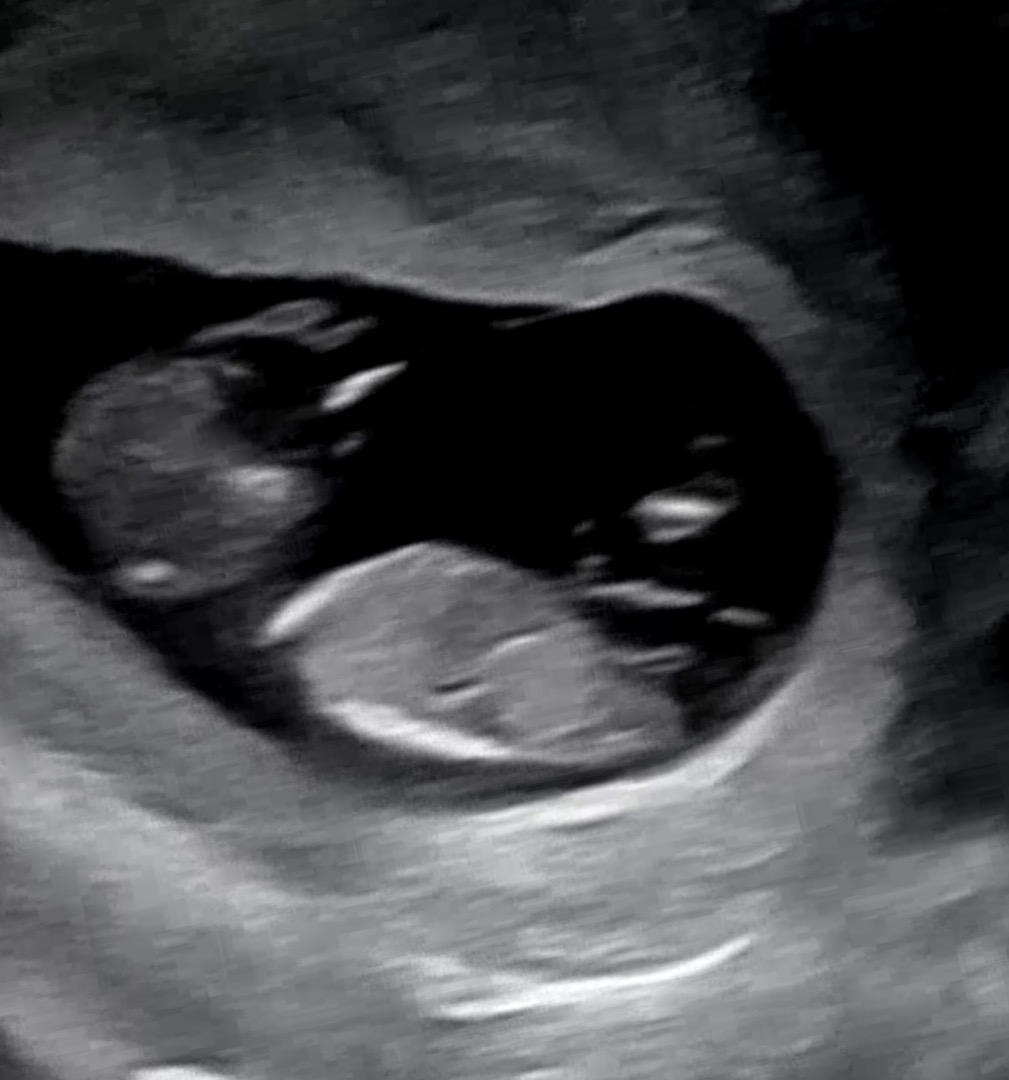

각도법 궁금해요🤣

장꾸맘님께서는 11주차라 반전 있을 수 있지만 지금은 아들 같다고 하셨고 지난 번 다른 사진 올렸을 때 맘님들께서 아들 같다고 하셨는데!!! 챗지피티나 다른 어플(?)에서는 딸 같다고 하고ㅋㅋㅋㅋ 저도 긴가민가해요ㅠㅠ 요 사진으로는 어때 보이나용??

아들같아요!!